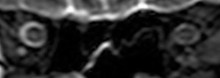

Intracranial pressure (ICP) needs to be directly measured before and after long duration flights to determine if microgravity causes the increased ICP. On the ground, lumbar puncture is the standard method of measuring cerebral spinal fluid pressure and ICP,[4][38] but this carries additional risk in-flight.[2] NASA is determining how to correlate ground-based MRI with inflight ultrasound[2] and other methods of measuring ICP in space is currently being investigated.[38]

The third case of visual changes while on board the ISS had no changes in visual acuity and no complaints of headaches, transient visual obscurations, diplopia or pulsatile tinnitus during the mission. Upon return to Earth, no eye issues were reported by the astronaut at landing. Fundus examination revealed bilateral, asymmetrical disc edema. There was no evidence of choroidal folds or cotton-wool spots, but a small hemorrhage was observed below the optic dics in the right eye. This astronaut had the most pronounced optic-disc edema of all astronauts reported to date, but had no choroidal folds, globe flattening or hyperopic shift. At 10 days post landing, an MRI of the brain and eyes was normal, but there appeared to be a mild increase in CSF signal around the right optic nerve.[3]